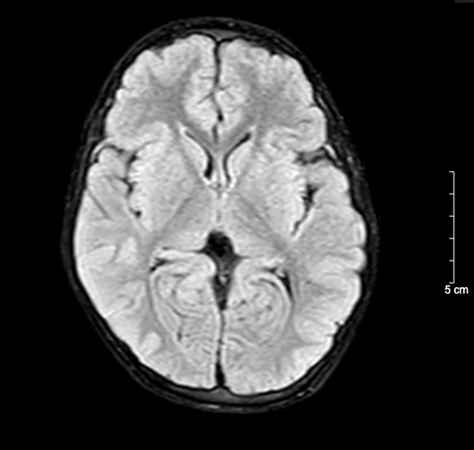

1746787230117.png1746787250787.png

Kết quả chụp não, cột sống cổ bệnh nhi sau 5 ngày nhập viện bình thường

BSCKII. Doãn Phúc Hải - Trung tâm Nhi khoa, Bệnh viện Bạch Mai trực tiếp điều trị cho bệnh nhi chia sẻ: Thân nhiệt của bệnh nhi được hạ nhanh xuống và kiểm soát duy trì ở mức 34°C, giảm tổn thương, tái tưới máu tại não, tăng tỉ lệ sống và hồi phục chức năng thần kinh. Sau 72 giờ điều trị hạ thân nhiệt chủ động, bệnh nhi được nâng thân nhiệt, làm ấm trở lại về mức bình thường và duy trì theo dõi trong 48 giờ. Khi thân nhiệt trở lại bình thường, bệnh nhi tỉnh dần và được rút ống thở. Dấu hiệu sinh tồn ổn định, tri giác nhận thức tốt. Sau 5 ngày nằm viện, bệnh nhi đã tỉnh táo hoàn toàn. Kết quả chụp tim, phổi, MRI sọ não, cột sống cổ không thấy bất thường. Đây cũng là trường hợp đầu tiên trẻ 5 tuổi tự “thắt cổ” mà chúng tôi bắt gặp.